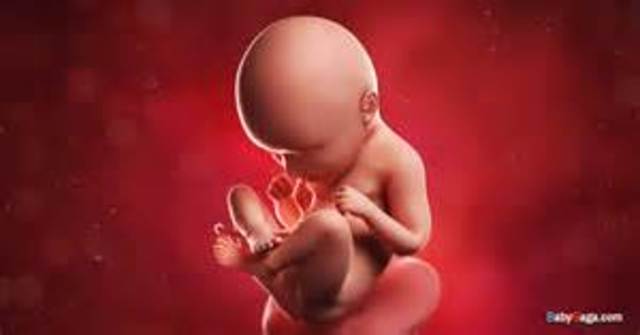

In week nine, the fingers and toes of the baby begin to develop; and it can now flex its elbows and wrists. Also during this week, the baby's head may appear larger than it's body due to the rapid growth of it's brain.

• Week 10

Week 10

In week ten, the baby becomes a fetus and all of its organs, nerves, and muscles begin to function within its body. During this week of development the fetus is about the size of a strawberry.,